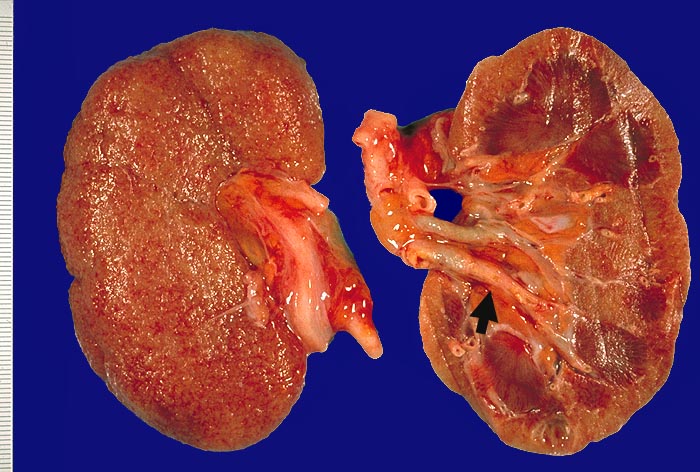

Noduläre Glomerulosklerose bei Diabetes mellitus Typ II

Niere

Gelbverfärbung der Schnittfläche. Oberfläche fein granuliert. Die Arterien sind bis weit in die Peripherie gut sichtbar aufgrund von Atheromen.

Termianale Niereninsuffizienz.